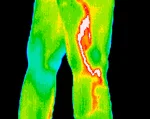

Region of Interest Thermography- $295.00

Region of Interest Thermogram: approximately 5–10 images that focus on one specific region of the body. This painless and non-invasive imaging is ideal for assessing injury and pain, determining the effectiveness of treatments and supplements, and viewing the body's healing process, without any radiation exposure.